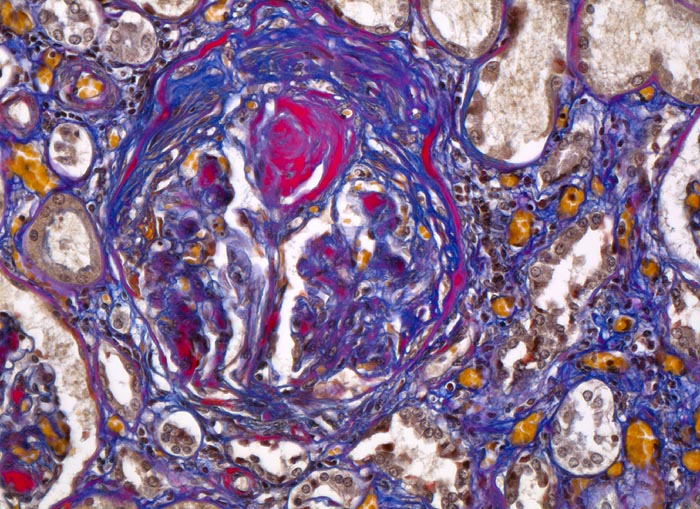

PathoPic ID 4636 - Diabetische noduläre Glomerulosklerose Kimmelstiel-Wilson

Diabetische noduläre Glomerulosklerose Kimmelstiel-Wilson

Systemerkrankung/Immunpathologie

Niere

Niere, Harnwege

Partiell verödetes Glomerulum mit

zwiebelschalenartig geschichtetem mesangialem Knoten. Interstitielle Fibrose.

Diabetes mellitus Typ II seit 20 Jahren.

Histologie

200